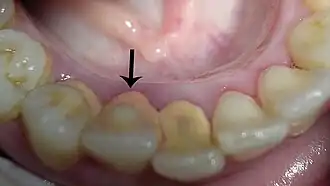

Cálculo supragengival

É clinicamente visível coronal à margem gengival. A presença e a quantidade do cálculo supragengival é o resultado do nível de depósitos bacterianos nos dentes, mas também são influenciados pela secreção da glândula salivar. Como resultado, a maior quantidade da placa supragengival é normalmente encontrada nas superfícies vestibulares dos molares maxilares adjacentes ao ducto da glândula parótida nas superfícies linguais dos dentes mandibulares anteriores, que estão expostos ao ducto das glândulas submandibulares.

O cálculo supragengival pode variar na cor, de branco ou amarela meio esbranquiçada, dependendo da coloração das substâncias alimentícias.

Dura como Argila, fácil remoção (pelos dentistas).